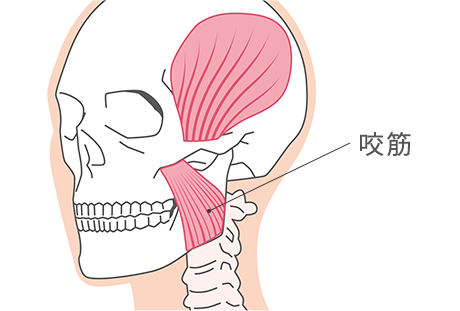

顎関節症や歯ぎしり・食いしばりなど、お顔の筋肉にまつわるお悩みにはボツリヌス注射で治療ができます。

お顔の周囲にはいくつもの筋肉があり、過度に緊張したり、肥大することで様々な悪影響を引き起こす恐れがあります。歯科医院で行うボツリヌス治療は、適切な部分にボツリヌス注射を行うことで、筋肉の強張りや肥大を和らげ、顎関節症や食いしばり、歯ぎりしなどの症状を緩和することが目的です。

ボツリヌス治療は注射を行う筋肉によって効果が異なります。当院では口腔機能の保全・予防に関する治療を行っています。

| 咬筋・側頭筋 | 咬筋肥大症、顎関節症、歯ぎしり・食いしばり、歯周病、咬合性外傷、咬合低位や酸蝕症による顎位不安定、咬筋緊張性疼痛、疲労感、緊張性開口障害など |

咬筋は、物を咀嚼する時に使われる筋肉の1つで、歯を食いしばった時に硬くなります。顎の外側にある筋肉で、硬い食べ物を噛み砕くときに機能します。

STEP 1

力を抜いてエラに手の平を置きます。

STEP 2

奥歯を強く噛み合わせて動く筋肉=咬筋を見つけます。

STEP 3

咬筋を優しく押して「硬い」と感じたら咬筋肥大の可能性があります。